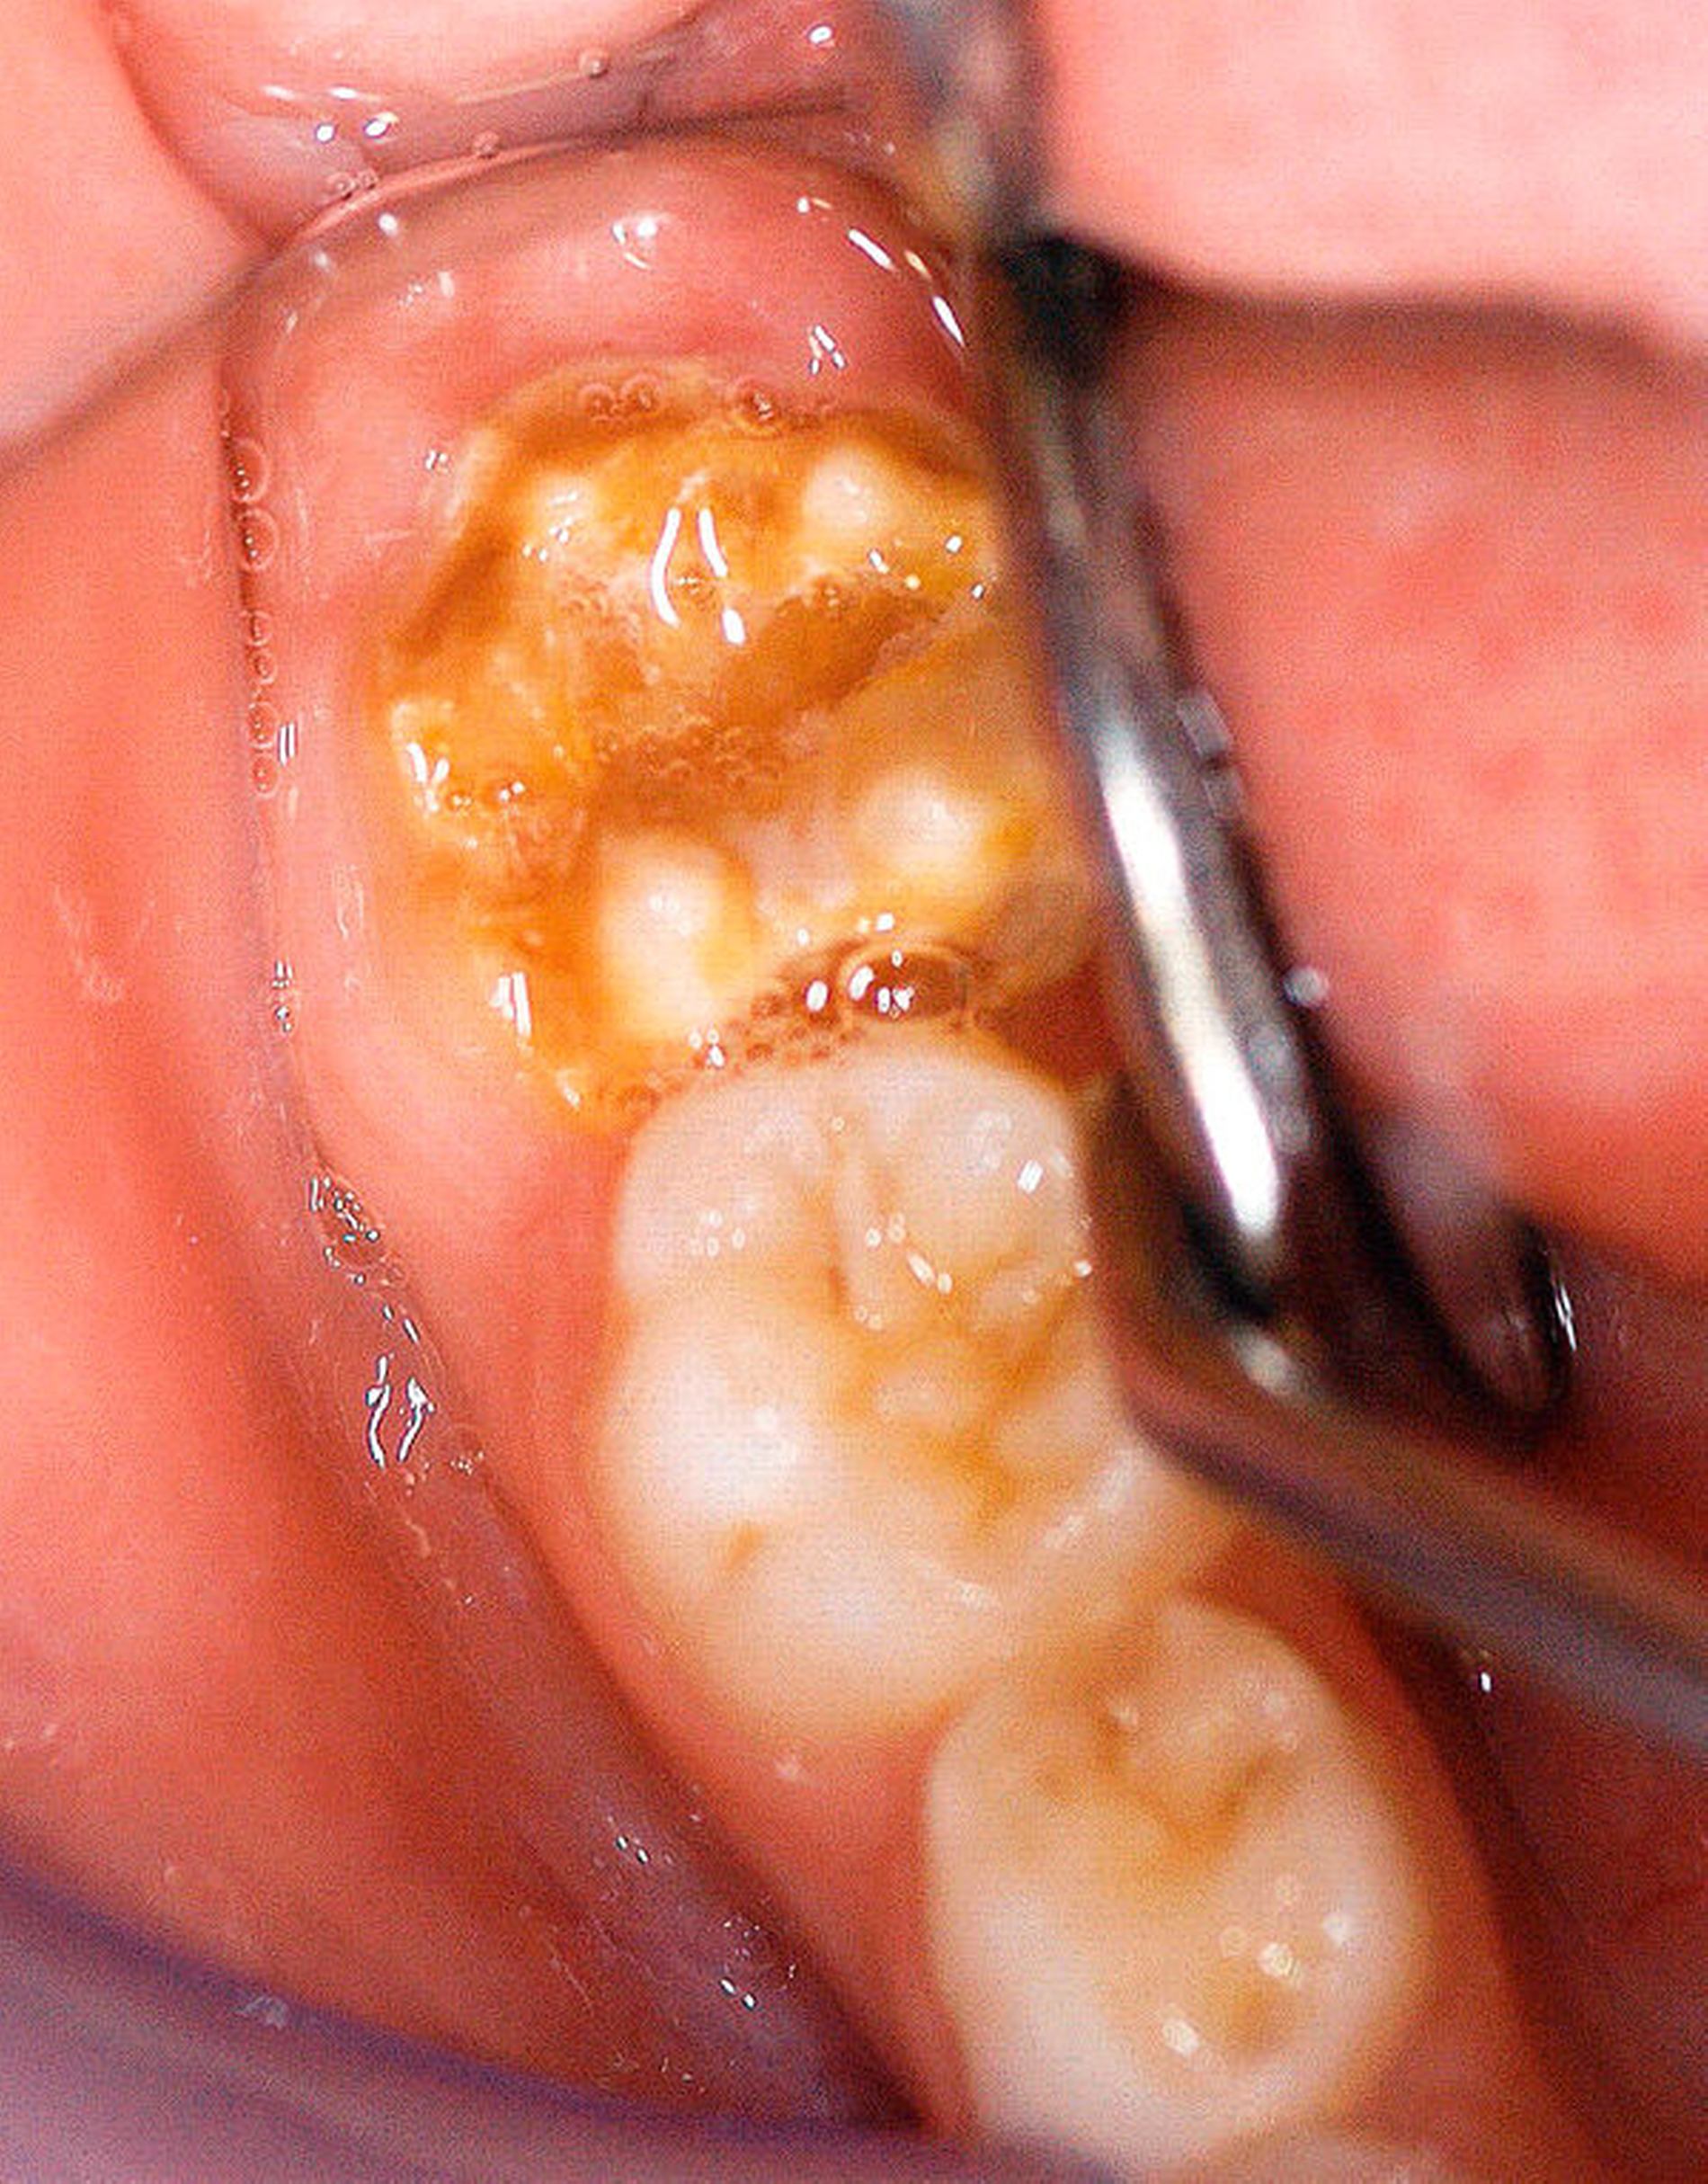

Die Ausprägung der Mindermineralisation kann stark variieren (Abbildungen 3 und 4). Klinisch zeigen sich an den betroffenen Zähnen unterschiedlich starke Verfärbungen beziehungsweise Opazitäten bis hin zu ausgeprägten Schmelzverlusten. So kann die Mineralisationsstörung im Bereich der Molaren auf einzelne Bereiche beschränkt sein, das Fissurenrelief einbeziehen oder sich über die gesamte Glattfläche erstrecken [Koch et al., 1987]. Bei den Inzisiven ist die Mindermineralisation bukkal zu finden. Geringgradig betroffene Zähne sind dabei eher durch weiß-gelbliche oder gelb-braune, unregelmäßige Verfärbungen gekennzeichnet, schwere Hypomineralisationsformen weisen dagegen abgesplitterte oder fehlende Schmelz- und/oder Dentinareale unterschiedlichen Ausmaßes auf.

Sind bei einem Patienten mehrere Molaren betroffen, so kann es auch hier zu Variationen kommen. Dementsprechend kann es sein, dass bei einem Molaren kleine, intakte Opazitäten zu finden sind, während an einem anderen Molaren große Teile des Schmelzes bereits kurz nach dessen Eruption einbrechen [Weerheijm, 2004].

Bildgruppe Abb. 7–14:Grade des MIH-Treatment-Need-Index im klinischen Erscheinungsbild